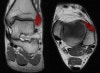

8. Achilles tendon

Axial T1W image assessing the normal Achilles tendon (red). Normally the Achilles tendon is concave or flat on axial imaging.

If it is convex or if it is >6 mm it is abnormal. Incidental accessory soleus muscle (green)